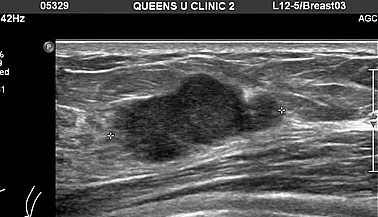

유방암 초기 증상으로 응어리나 멍울이 만져지면 유방암 초기 증상을 의심해보아야 합니다. 가슴이나 겨드랑이 방향을 손으로 만졌을 경우 울퉁불퉁한 혹이 느껴진다면 의심해 보아야 합니다. 악성 종양인 경우 일반적으로 단단하고 고정되어 이동하지 않고 모양이 불규칙합니다. 하지만 멍울은 유선 내에 있는 혹으로, 90%가 양성 진단을 받는 것으로 알려져 있습니다. 이러한 응어리 멍울은 유방암과 관계없는 섬유선종이나 섬유낭종일 가능성도 높아 의료기관에서 정확히 진찰받는 것이 좋습니다.

유방암 초기 증상 3. 가슴 통증

이는 유방 내부에 생긴 종양이 자라면서 유방 조직과 가슴에 압박을 가해서 통증을 발생하는 것일 수 있습니다. 이외도 과도한 스트레스나 피곤함, 수면부족 등 다양한 상황에 따른 호르몬 변동의 이유로 진통이 나타날 수 있어 통증이 심해지거나 유지된다면 의료기관에 방문하여 정확하게 검진을 받아 보시기를 권장합니다.